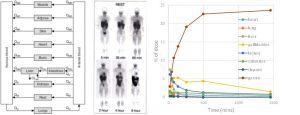

Τίτλος Ερευνητικού Έργου: Βελτιστοποίηση της ανάπτυξης φαρμάκων με μεθόδους μοντελοποίησης και προσομοίωσης

Επιστημονικός Υπεύθυνος: Δοκουμετζίδης Αριστείδης